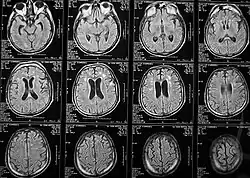

Магни́тно-резона́нсная томогра́фия (МРТ) — способ получения томографических медицинских изображений для исследования внутренних органов и тканей с использованием явления ядерного магнитного резонанса. Способ основан на измерении электромагнитного отклика атомных ядер, находящихся в сильном постоянном магнитном поле, в ответ на возбуждение их определённым сочетанием электромагнитных волн. В МРТ такими ядрами являются ядра атомов водорода, присутствующие в огромном количестве в человеческом теле в составе воды и других веществ[1].

Томография позволяет визуализировать с высоким качеством головной, спинной мозг и другие внутренние органы. Современные технологии МРТ делают возможным неинвазивно (без вмешательства) исследовать работу органов — измерять скорость кровотока, тока спинномозговой жидкости, определять уровень диффузии в тканях, видеть активацию коры головного мозга при функционировании органов, за которые отвечает данный участок коры (функциональная магнитно-резонансная томография — фМРТ).